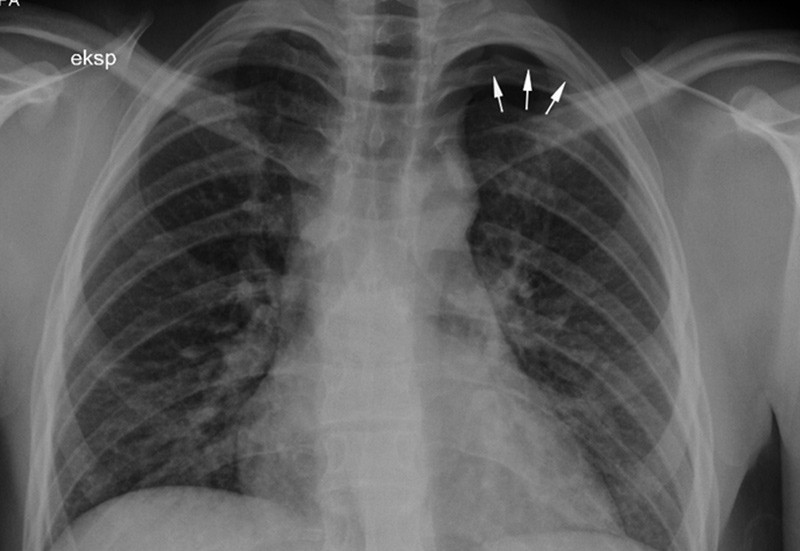

Opplysninger om dette førte til ny gjennomgang av innleggelsen i vårt sykehus. Ved nøye inspeksjon av røntgenbildene av lungene kunne vi se en liten, apikal luftkappe på venstre side som målte ca. 12 mm i ekspirasjon (fig1).

Vanlig stående røntgen thorax med posterioanterior strålegang er vanligvis nok for å stille diagnosen pneumothorax. Bilder tatt i ekspirasjon anbefales ikke som del av vanlig rutineutredning (12). Små luftkapper kan være vanskelige å oppdage, og det er fort gjort å overse en liten pneumothorax, spesielt dersom man ikke aktivt leter etter en. På stående bilder ses vanligvis en apikal hyperklar sone med synlig kontur av viscerale pleura og manglende kartegninger perifert. På liggende bilder kan det være vanskeligere å diagnostisere en pneumothorax siden luften stiger opp mot det høyeste punktet og dermed legger seg anteriomedialt mot basis av lungen (16).